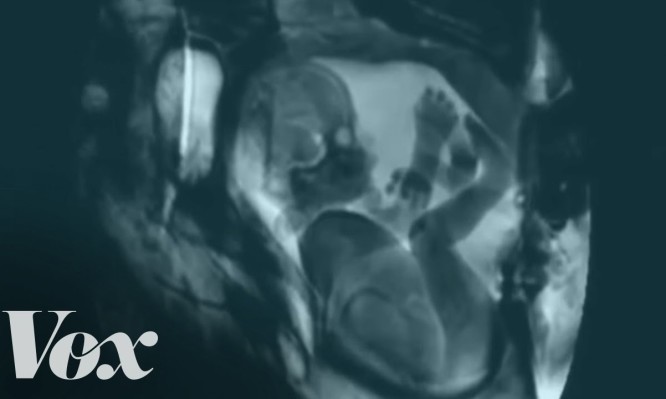

Τι συμβαίνει μέσα στο σώμα όταν τρώμε μιλάμε ή κάνουμε… (ΒΙΝΤΕΟ)

Σε κάποια φάση της ζωής μας, όλοι έχουμε αναρωτηθεί τι συμβαίνει πώς θα ήταν να μπορούσαμε να δούμε τι...